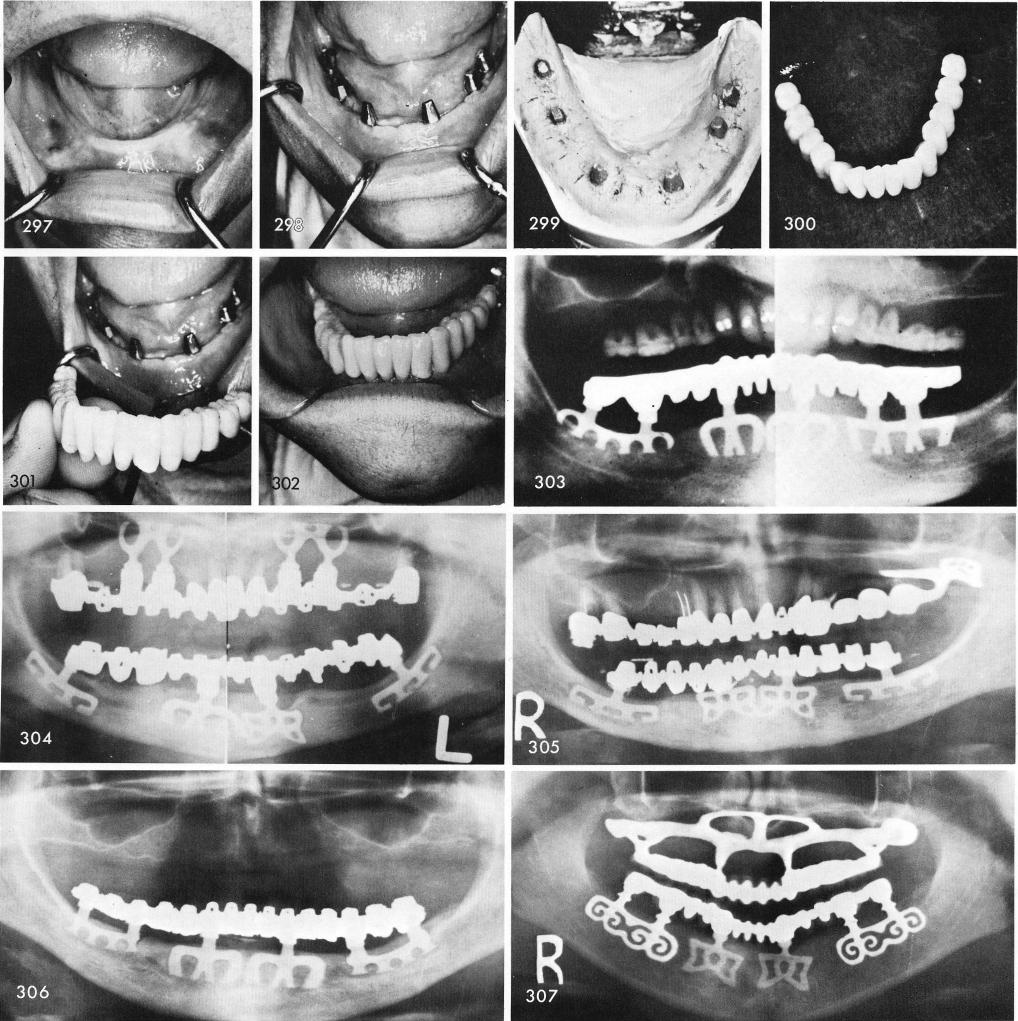

A totally edentulous case, fig. 297, with bladevents, fig. 298, can rapidly be completed with the use of a one piece elastic impression into which epoxy dies can be fashioned, fig. 299. A porcelain full arch prosthesis was the restoration used in this case, figs. 300, 301, 302. The post-operative x-ray, fig. 303.

Figs. 304 through 312 show x-rays of totally edentulous mandibular blade cases.